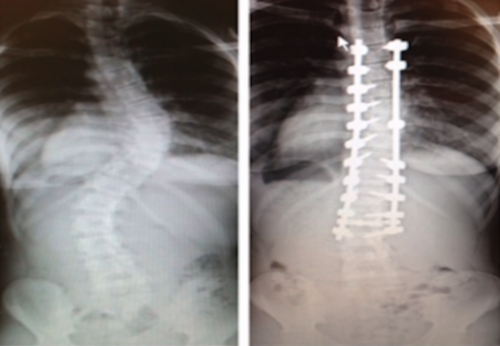

After finding out she had scoliosis, 12-year-old Siara underwent spine surgery and returned to cheerleading.

Sometimes scoliosis can be corrected without surgery; however, that wasn’t the case for Genova’s severe curve.